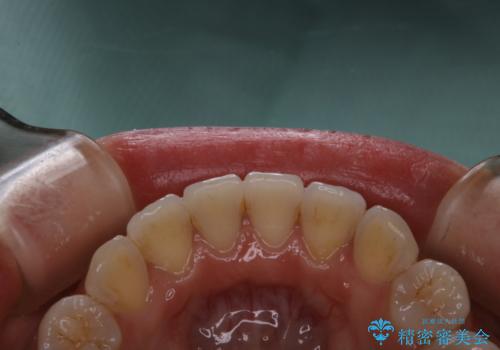

invisalignでの矯正治療が終了した方のPMTC

- 当院でのインビザライン矯正治療が終了し、メンテナンスにいらしている方です。PMTC30分コースを行いました。

矯正治療が終わり、せっかくきれいになった歯並びも、虫歯・歯周病などになってしまっては元も子もありません。

ご自身での歯ブラシ・セルフケアを行うと同時に、定期的なクリーニング(PMTC)を行うことで、いつまでも健康な歯を保つことができます。